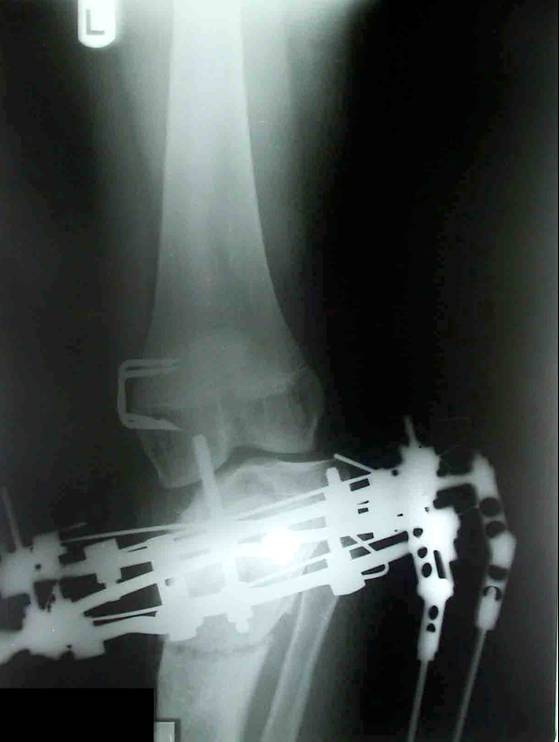

Blount disease is a developmental disorder characterized by disordered growth of the medial aspect of the proximal tibial physis resulting in progressive lower limb deformity. The deformity consists of varus, procurvatum, and internal rotation of the tibia, However, in the advanced stage of the disease, there is a bony bridge formation with medial plateau depression, joint instability, and leg length inequality, all of which have to be addressed by the proposed treatment. We treat this case by intra atticular osteotomy to elevation of medial plateau and another metaphyseal osteotomy to correct the varus and internal rotation deformities.

داء بلونت يطلق علي اعوجاج الساق المكون من هبوط باعلي الجزء الداخلي من اعلي عظمه الساق مع اعوجاج انسي بالساق و يتم علاج تلك الحالات بواسطه شقين عظميين احدهما خلال غظروف اعلي عظمه الساق والاخر بالجزء العلوي للساق مع الاستعدال التدريجي بواسطه مثبت خارجي مع العلم ان العلاج لا يرتبط بوزن المريض حيث يتم عمل العمليات بنجاح في الحالات السمنة الشديدة كما هو موضح بالصور